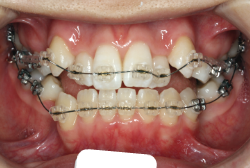

叢生(そうせい)

凸凹な歯並びのことを叢生といいます。矯正歯科に来院する患者様の主訴の中で、最も多いのが「配列の凸凹を真っ直ぐにしたい」というものです。歯の大きさと顎の大きさの調和がとれていないことが原因です。

凸凹を主体としたケースの場合、当院の平均治療期間は18ヶ月ですので、このケースは少し長めに経過しました。理由の一つは凸凹の程度がかなり重症だったと言うことですが、もう一つは、右下第2大臼歯が45度くらい前傾していたため、それを整直化させるために時間を要したと考えています。いずれにしても最終結果は大変よい状態と思います。

治療前は並びが乱れて見た目が悪いというのはもちろん問題ですが、歯科医学的に一番困るのは噛み合わせが悪いという点です。上下の犬歯(3番目の歯)は、上下的に離れた位置にあるため接触することができません。つまり歯としては存在していても、歯としては機能していないということです。